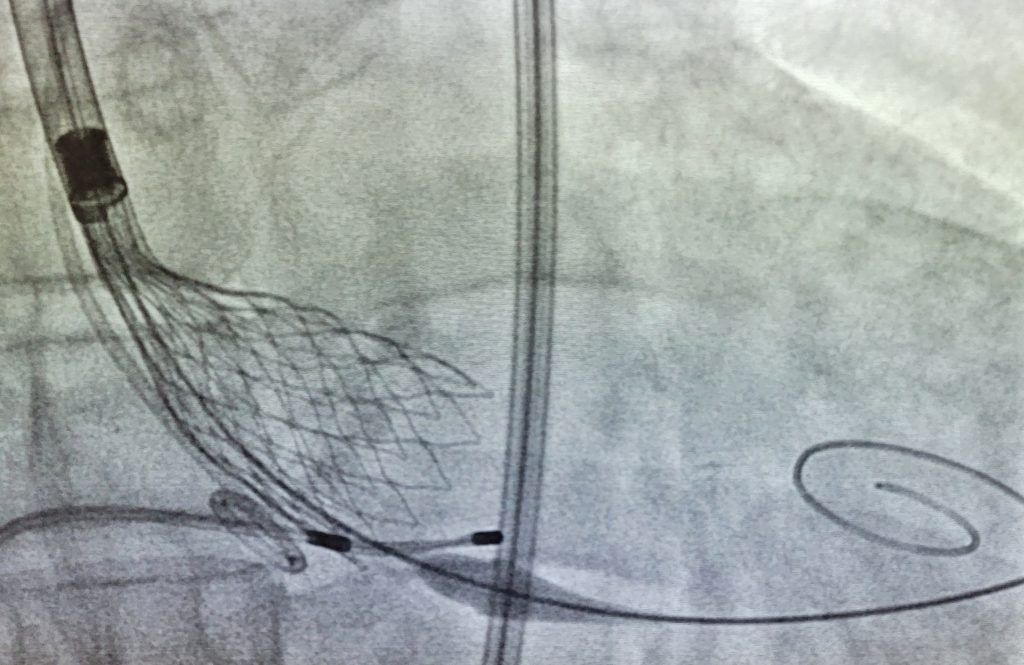

Shunts cardíacos

Alguns pacientes podem nascer com defeitos de comunicação entre as cavidades do coração, isso pode proporcionar uma passagem indesejada de sangue de uma cavidade para outra ("shunts"). Entre os mais comuns está a comunicação interatrial (CIA) que pode ser fechada com uma prótese implantada por catéter na sala de hemodinâmica.